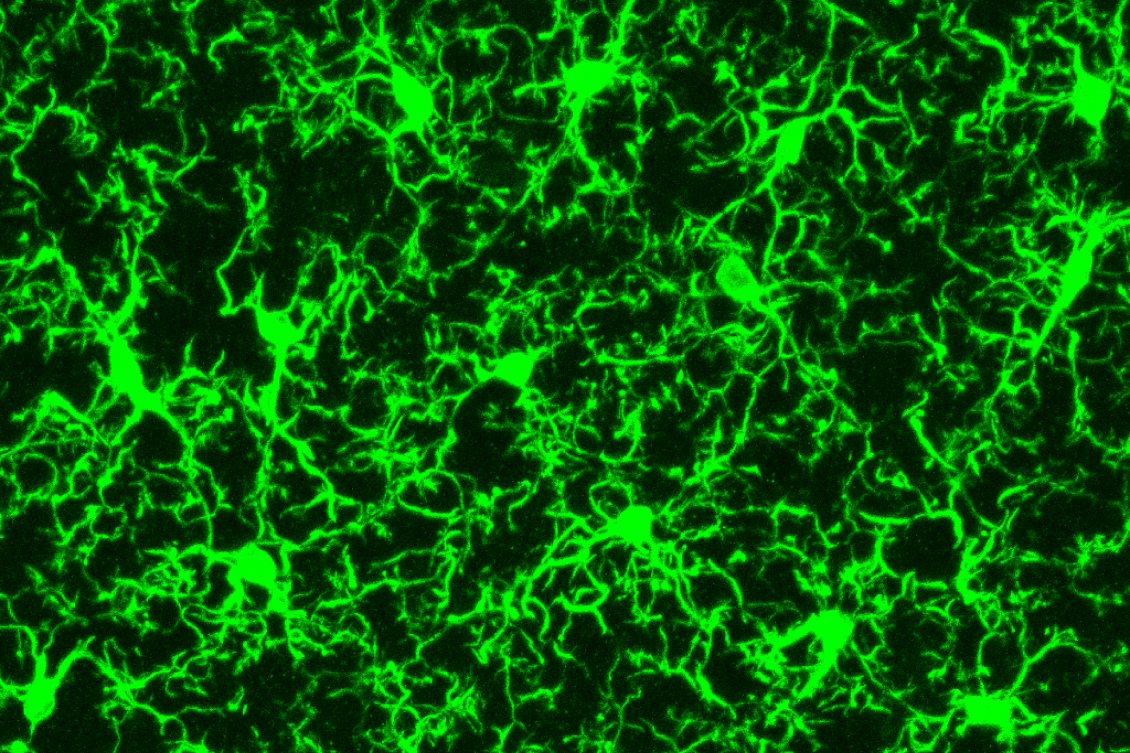

Microglia, immune cells that act as the central nervous system’s damage sensors, have recently been implicated in Alzheimer’s disease.

The cells, a type of macrophage that clear away dead cells from the brain and help to maintain healthy neuronal wiring, were found to be entangled with toxic amyloid beta plaques in tissue taken from those suffering from the disease.

To find out if these distinct types of microglia overlap geographically, the researchers then performed a technique known as immunostaining to investigate where the populations of cells were distributed in the mouse brain. They stained different sections of the mouse hippocampus with antibodies that recognise particular gene products.

They found that the different types of microglia have very different distribution patterns.